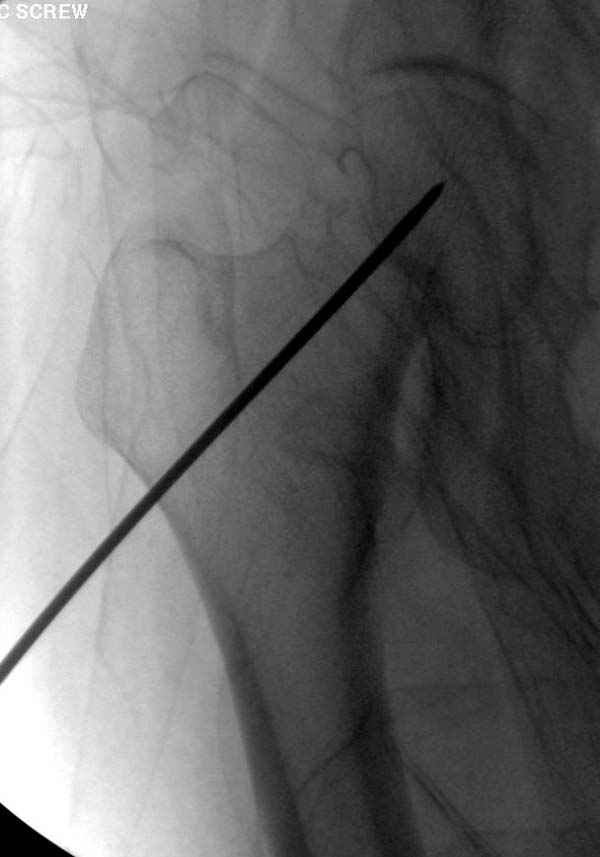

вопрос вне контекста: при введении каннюлированных

винтов как часто пользуетесь гайдом? и пользуетесь ли вы им всегда?

Я имел ввиду параллельный направитель,

обеспечивающий параллельное расположение винтов. к

сожелениию не смог найти точное название на англ.

Наверное речь идет насчет parallel guide из набора. Применяем по возможности всегда, но,

как видно на снимке, не всегда получается

паралельно.

Такие несмещенные переломы обычно для молодых резидентов, и бывают технические неточности, но в этом случае посчитали фиксацию адекватной.

Соблюдая правила, многократными попытками можно

увеличить риск стрессового перелома латерального

кортекса.